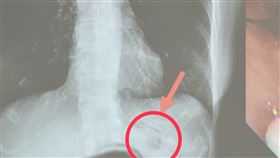

44歲男乳頭流膿 X光驚見「刀插胸腔8年」

國外一名44歲男子因為「乳頭流膿」到醫院就診,然而除...